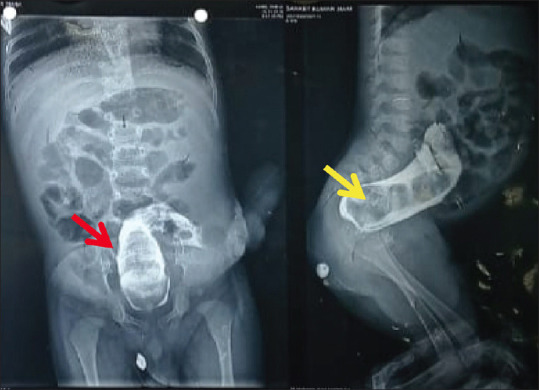

Delayed Complete Colonic Stricture after Posterior Sagittal Anorectoplasty: Iatrogenic or Inflammatory?